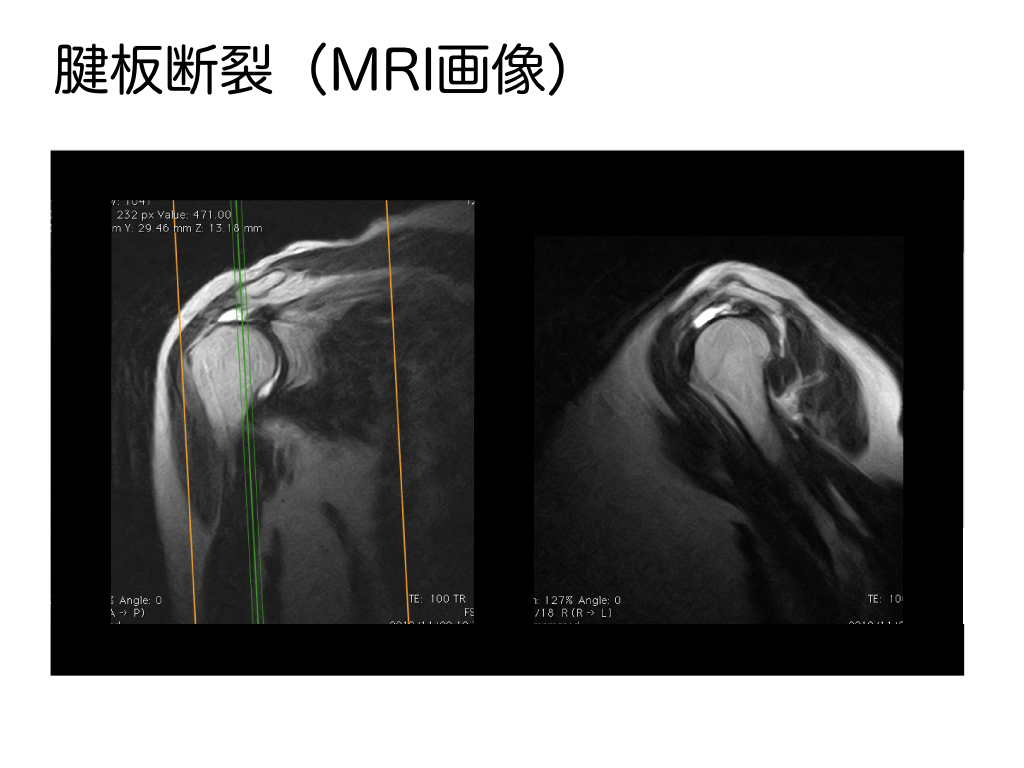

腱板断裂を確定診断するためにはMRIが有用であり、上記はT2強調画像ですが、棘上筋腱の部分が白くなっていることがわかります。

炎症がある(水が溜まっている)時点で断裂が疑われますので、そのようなケースではなにがストレスとなって損傷したのかを見つけることが大切です。